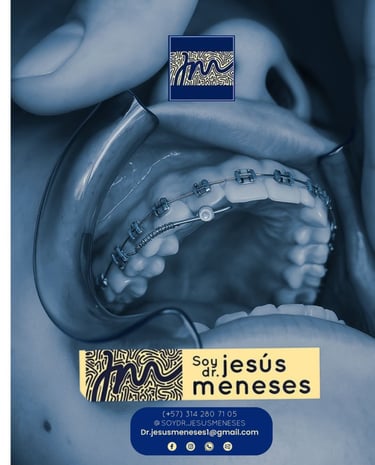

Ortodoncia

Alineamos tus dientes con tecnología avanzada para resultados naturales.

Galería

Sonrisas reales y tecnología en acción